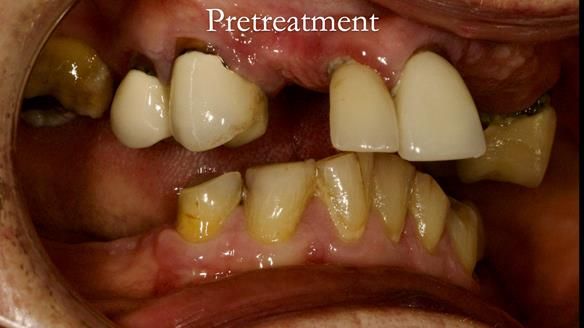

Aesthetically and functionally poor RPDs were replaced for Eileen, a 74 year old woman.

Referred to me by her general dental practitioner specifically for replacement RPDs.

Dental concerns

“Top denture loose making conversation difficult at times. Also, appearance isn’t good. Teeth uneven”

Diagnoses

- Missing teeth in the upper and lower jaws

- Upper and lower metal based RPDs, poorly fitting, worn occlusal surface, reverse curve aesthetics, lacking support

- Poor dental appearance with reverse incisal curve

- The upper right central and lateral incisors with post crowns. Healthy and functionally secure but with poor appearance, contributing to the reverse curve.

- Moderate to heavily restored dentition with deep overbite (Class 2 div II)

- Yellowish lower front teeth with small amount of wear.

- The lower right canine (LR3) is worn with MOD cavity.